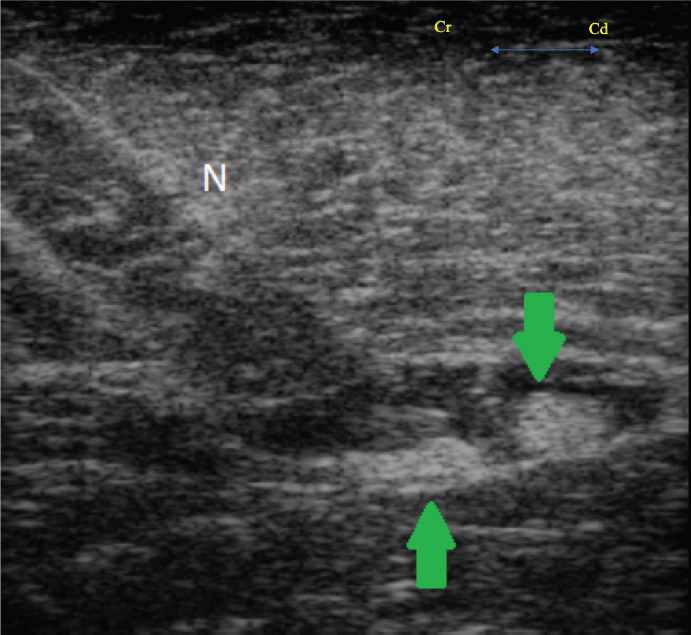

For provision of the PNBs, a total of 0.3 ml/kg (2.25 mg/kg) of ropivacaine (Naropin ®0.75%, AstraZeneca, Cambridge, UK) was drawn up, with 0.1 ml/kg utilized for the SN block and the remaining 0.2 ml/kg utilized for the PsC block. The ultrasound guided SN block was performed using a portable ultrasound system (MyLab 30, Esoate, Genova, Italy) as described by Echeverry et al. (2010), using a 22G 63 mm Quincke spinal needle (Figs. 1 and 2). With the transducer placed distal to the trochanter major in a transverse plane, the SN was identified as two ellipsoid structures surrounded by a thin hyperechoic rim deep to the biceps femoris muscle. The needle was advanced in-plane and the nerve approached in a transverse view. The LA solution was injected after aspirating, to rule out intravascular needle placement. Correct positioning was confirmed by spread of LA solution around the circumference of the nerve.

Fig. 2. Transverse ultrasound image showing the needle (N) and the sciatic nerve (arrows), identified as two ellipsoid structures deep to the biceps femoris muscle.